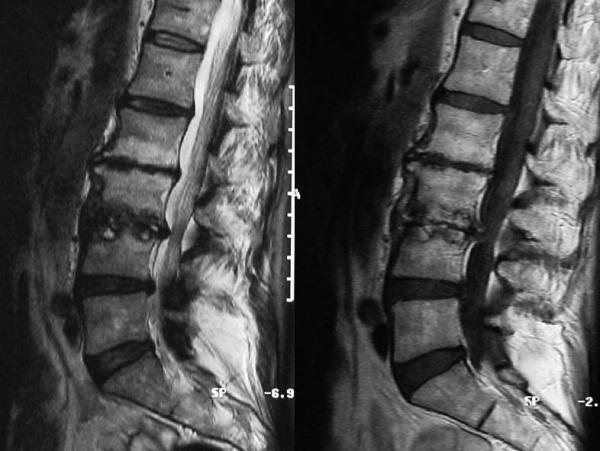

Die perkutane Fixation ist eine elegante Methode, mit der eine notwendige Versteifung direkt durch die Haut vorgenommen wird ohne große Schnitte. Die Methode ist leider nicht für jede Form der Fixation geeignet. Insbesondere ist es schwierig eine Reposition vorzunehmen, d. h. eine Korrektur, wie sie beispielsweise beim Wirbelgleiten notwendig ist. Für das so genannten Postdiscektomie-Syndroms, d.h. Mikroinstabilitäten nach Bandscheibenoperation und für Frakturen sowie Entzündungen ist sie jedoch die Methode der Wahl. Hierbei werden mit reinen Punktionstechniken unter Röntgenkontrolle Schrauben in die Wirbelkörper eingebracht. Danach kann noch distrahiert, d.h. gedehnt werden und abschließend werden die Schrauben mit Stangen verbunden und mit Muttern befestigt.